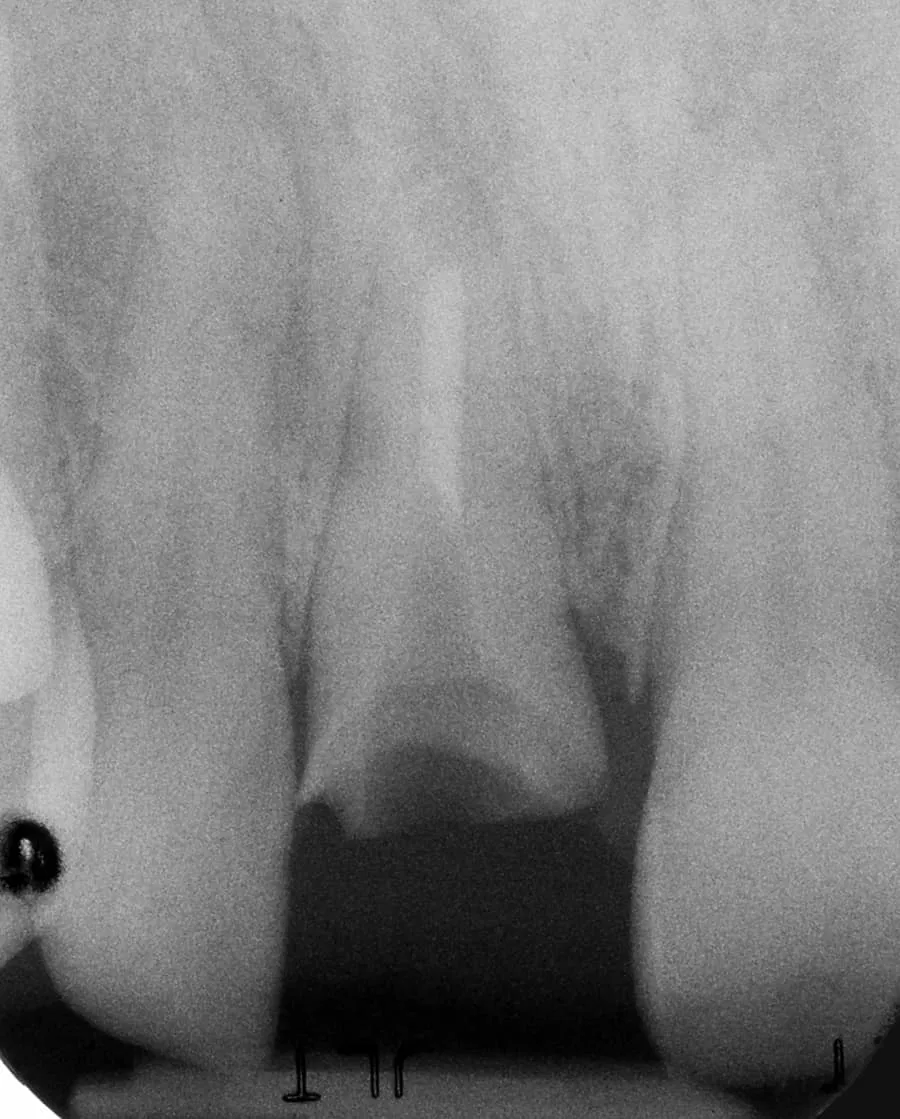

Before:Â Fractured/failed heavily treated upper right central incisor (tooth #8). The root is non-restorable and requires removal. The treatment of choice is a single implant supported restoration.